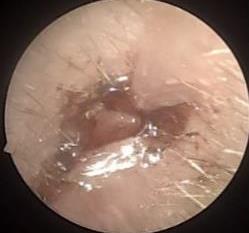

• 耳内镜下耳屏软骨-软骨膜鼓膜修补术后的短期疗效观察

摘要:目的 探讨耳内镜下耳屏软骨-软骨膜鼓膜修补术后的短期疗效。方法 回顾性分析2019年9月-2022年8月该院收治的78例鼓膜穿孔患者的临床资料,患者均采用耳内镜下鼓膜修补术。术后随访3个月,观察鼓膜形态和穿孔愈合情况,记录内镜图像、干耳时间、术前术后听力及耳鸣情况,以及外耳道狭窄等并发症的发生率。结果 术后3个月,鼓膜穿孔愈合率为97.44%(76/78),愈合良好,平均气导听阈较术前明显改善,气骨导间距较术前明显缩小,耳鸣较术前明显改善,差异均有统计学意义(P<0.05)。干耳时间为(4.21±1.12)周。术后出现肉芽5例,再穿孔2例,真菌感染2例,术腔感染、耳屏感染、外耳道狭窄和切口瘢痕各1例,所有患者术后均未发生面神经麻痹和感音神经性聋等严重并发症。结论 耳内镜下耳屏软骨-软骨膜鼓膜修补术是一种安全、有效的手术方法。根据术后愈合规律、内镜下鼓膜和外耳道形态特征,可为鼓膜修补术后正常中耳转归和并发症的诊疗,提供临床参考。